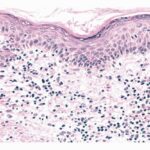

Histopathology. The small-plaque parapsoriasis shows focal epidermal involvement consisting of slight spongiosis, exocytosis of lymphocytes, mild acanthosis, and parakeratosis . Elongated mounds of parakeratosis with collections of plasma above a basket-weave cornified layer is a characteristic finding . In the papillary dermis, there is a mild superficial perivascular lymphocytic infiltrate that in some instances is more pronounced and resembles that seen in the large plaque type; such cases require inclusion in the largeplaque category . It must be conceded that, in some instances, a clinical or histologic distinction of small-plaque parapsoriasis from large-plaque parapsoriasis is difficult, so that only the subsequent course decides the issue . |

Pathogenesis. The inflammatory infiltrate in small-plaque parapsoriasis is dominated by CD4+ (helper-inducer) T lymphocytes with a small proportion of the CD8+ (cytotoxic-suppressor) |

T lymphocytes subset. Langerhans cells are increased in the epidermis and dermis . |